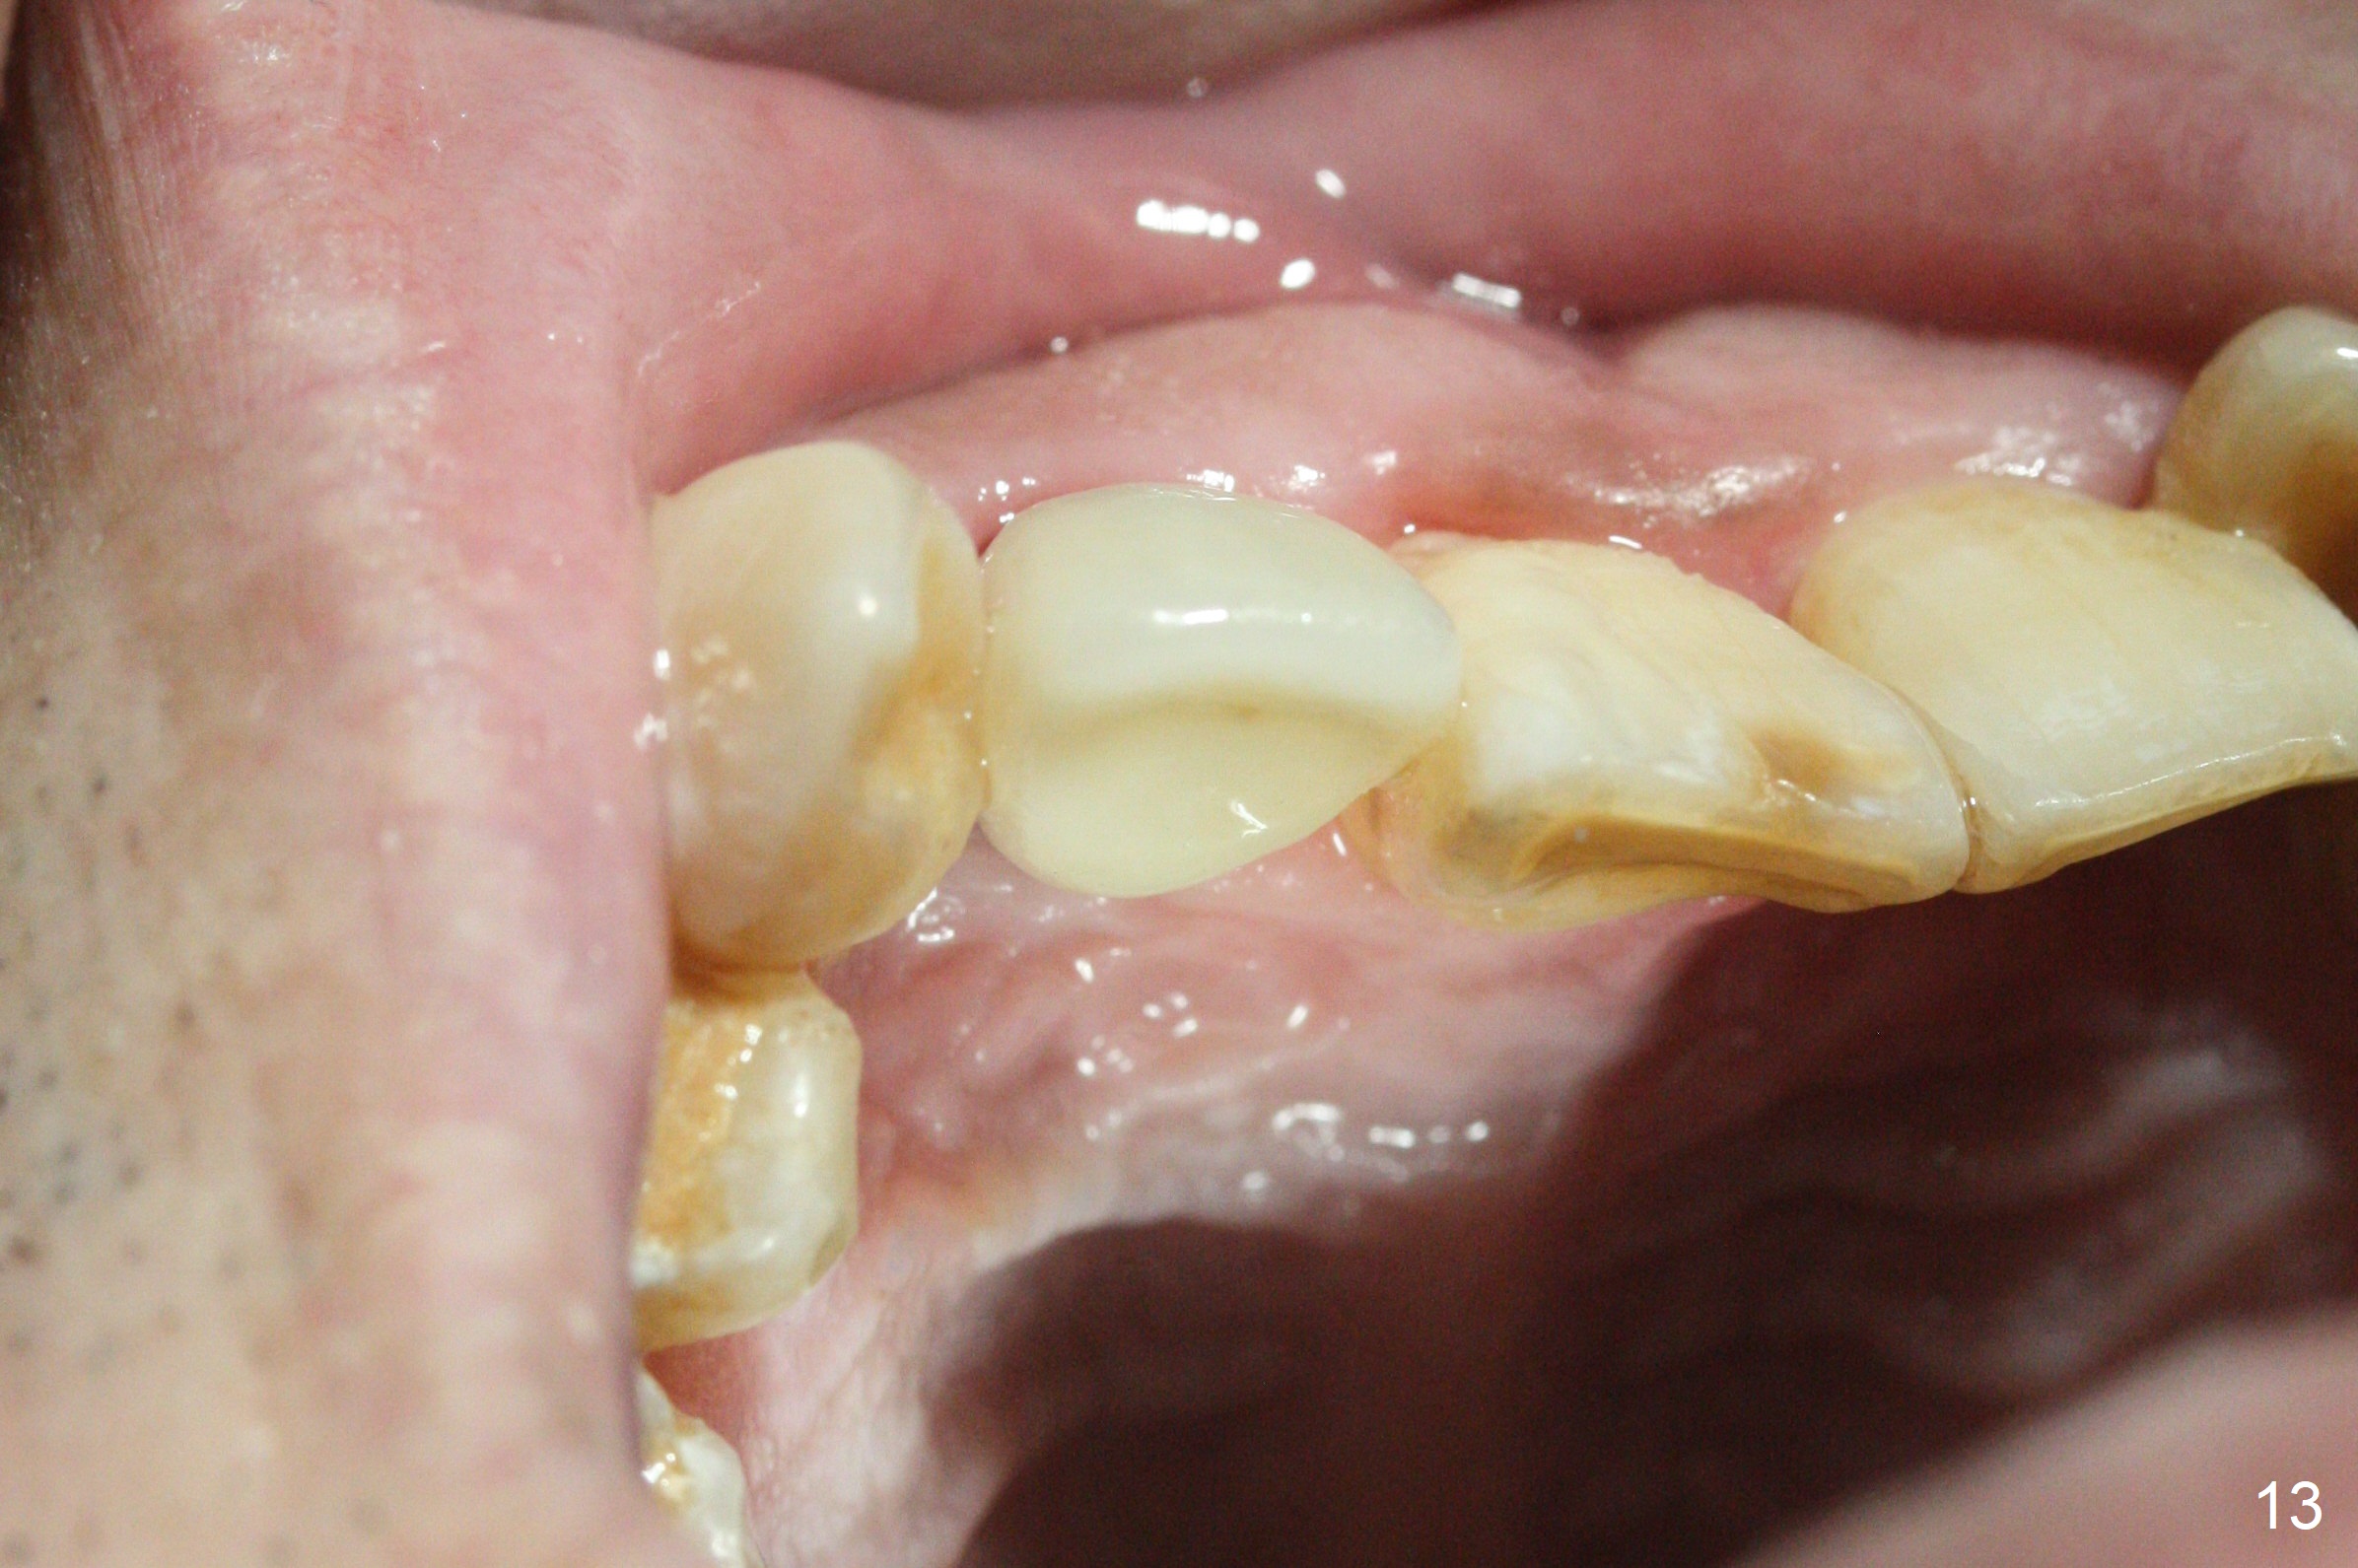

Sixteen days postop, the patient is doing fine, although the labial fistula has not disappeared (Fig.8 <). The detached distolabial papilla is healing (Fig.9 *) with mild bone graft exposure (^). The lacerated distopalatal papilla is also healing (Fig.10 *). These complications are related to flap surgery. The apical portion of the socket appears to have reduced 4 months postop (Fig.14). When the definitive restoration is delivered 5 months postop, there is gingival recession, including the distal of #8 (Fig.11 arrows, which is expected to improve over time) due to flap surgery. The labial plate collapse is minimal (Fig.12 *), while the palatal laceration (Fig.10) has healed (Fig.13). When the patient returns 1.5 years post cementation, there is increased bone density next to the coronal portion of the implant, equivalent to the bone graft (Fig.15 *). The fistula is absent (Fig.16). The crestal bone loss remains 2.5 years post cementation (Fig.17 *), although there is no sign of periimplantitis (magnification). Oral hygiene is poor. There is no change in the soft (gingival recession; data not shown) or hard tissues 3 years 8 months post cementation (Fig.18).